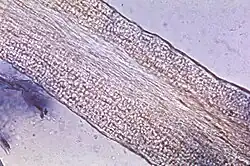

Nativpräparat der Veränderungen eines Haars infolge der Infektion mit Trichophyton tonsurans

Zur weiteren Untersuchung wird das Hornmaterial auf einem Objektträger mit 15–20%iger Kalilauge (KOH) überschichtet, um die Pilze aus dem Horn herauszulösen. Die Einwirkzeit beträgt etwa eine halbe Stunde, durch vorsichtiges Erwärmen kann der Vorgang beschleunigt werden. Um eine Auskristallisation zu vermeiden, sollte die Probe in einer feuchten Kammer gelagert werden. Unter einem Mikroskop lassen sich die Pilzhyphen und/oder Sporen nachweisen. Gegebenenfalls kann zur Dermatophyten-Anfärbung der Kalilauge Methylenblau zugesetzt werden. Etwas einfacher ist der Nativnachweis mit Fluoreszenzfarbstoffen wie z. B. Acridinorange unter einem Fluoreszenzmikroskop.[33]